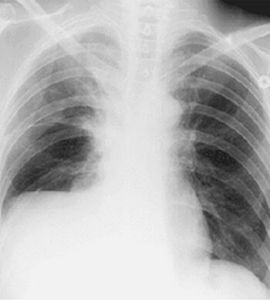

穿刺選在胸部叩診實音最明顯部位進行,一般常取肩胛線或腋後線第7-8肋間;有時也選腋中線第6-7肋間或腋前線第5肋間為穿刺點。包裹性積液可結合X線或超音波檢查確定。穿刺點可用蘸龍膽紫的棉簽在皮膚上做標記。操作要點

1.體位 患者多取坐位。面向椅背,兩手交叉抱臂,置於椅背,頭枕臂上,使肋間隙增寬;不能坐起者,可採取半臥位,舉起患側上臂2.穿刺部位 選擇叩診實音、呼吸音消失的部位作為穿刺點,一般常選腋後線與肩胛下角線之間第7~9肋間;或採用超音波檢查所定之點。